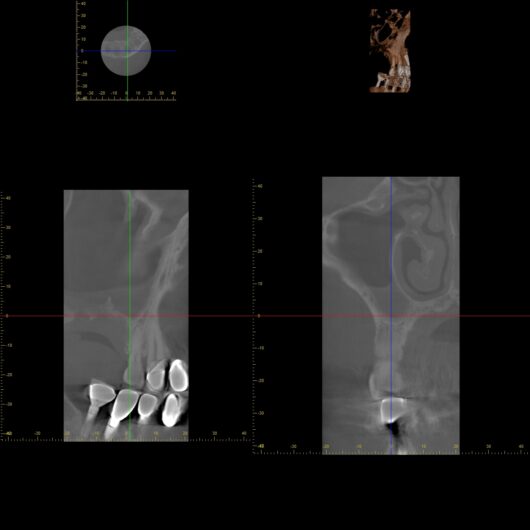

あんなに患者さんを苦しめていた頭痛は、霧が晴れるように消えていきました。再撮影したCT画像では、真っ白だった上顎洞が本来のクリアな黒い影へと戻り、炎症がきれいに消失していることが確認できました。

(※術後の綺麗なCT写真)